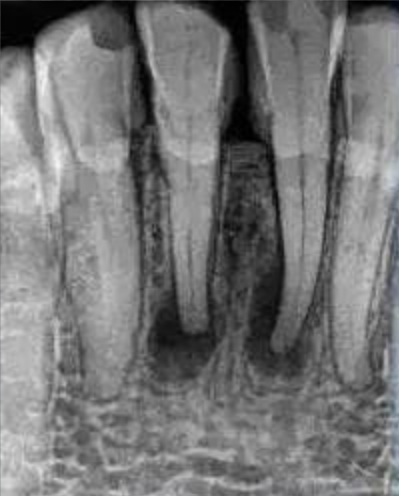

1. 确定感染的范围:通过牙齿的X光片,牙医可以确定感染是否已经扩散到牙根尖周围的组织。这有助于医生制定适当的治疗计划,并决定是否需要进一步的检查或手术。

2. 评估牙齿的结构:X光片可以帮助医生评估牙齿的整体结构,包括牙髓腔的大小、根管的数目形态和位置。这对于确定是否适合进行根管治疗以及选择合适的治疗方法非常重要。

3. 检测潜在的问题:除了感染外,X光片还可以帮助医生检测其他潜在的问题,如根尖的囊肿、牙齿断裂或移位等。这些问题可能需要额外的治疗或手术干预。